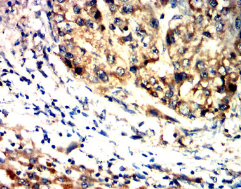

IHC    1/200 - 1/1000